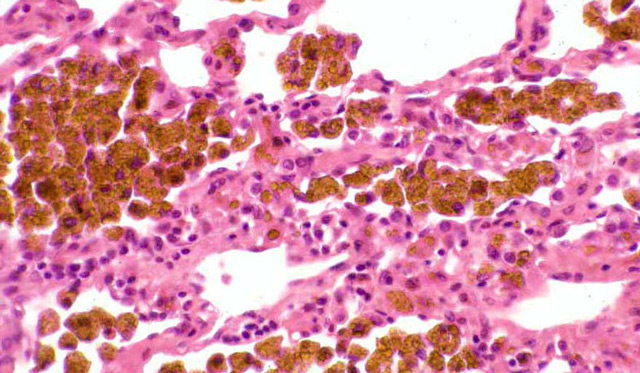

Отложения гемосидерина в тканях (идиопатический лёгочный гемосидероз)

Гемосидероз легких — это заболевание с неясной причиной, характеризующееся тяжелым хроническим течением. У пациентов часто наблюдаются повторные кровоизлияния в альвеолы, что приводит к распаду эритроцитов в легочной ткани и выделению значительного количества гемосидерина. Эти процессы ухудшают способность легких выполнять свои основные функции.

Во время аутопсии у ряда пациентов выявляется бурая индурация легких, которая редко диагностируется при жизни. В крови таких больных образуются аутоантитела — комплекс антител и антигенов. Это вызывает воспалительную реакцию, локализующуюся в легких, так как их ткань становится целью для аутоантител. Мелкие сосуды, пронизывающие легочную паренхиму, расширяются, из них выходят эритроциты, распадающиеся в легочной ткани, что приводит к избыточному накоплению гемосидерина.